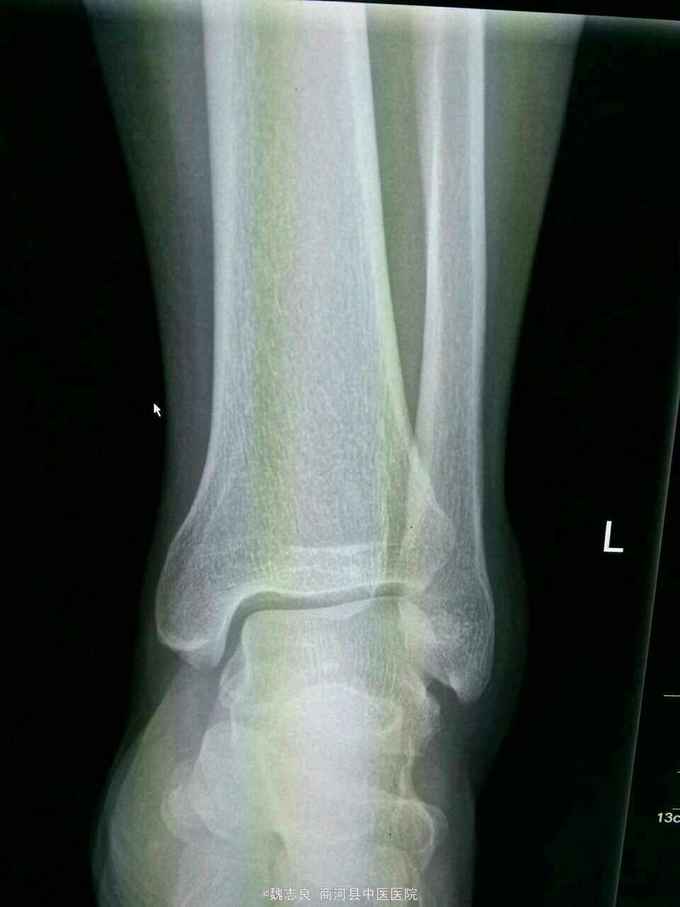

X线表现:正位像未见骨折征象,侧位像左外踝骨折。CT证实为内踝骨折。提醒我们关节内的骨折以及高度怀疑骨折的患者应该做ct检查,避免漏诊。